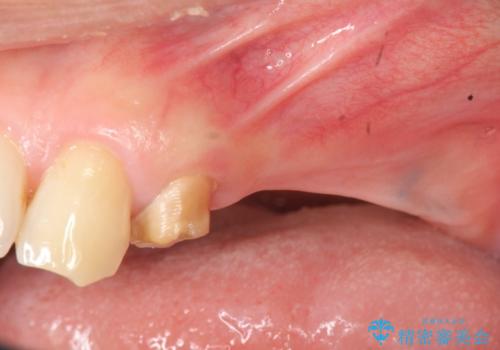

- 重度の虫歯により左上の歯を失い、インプラント治療は怖いため嫌厭して放置していたが、いよいよ食事に困りしっかりと噛めるようになりたいと希望され来院されました。

残存している小臼歯も虫歯が大きく保存が難しいため抜去を行い造骨を含めたインプラント治療を行います。